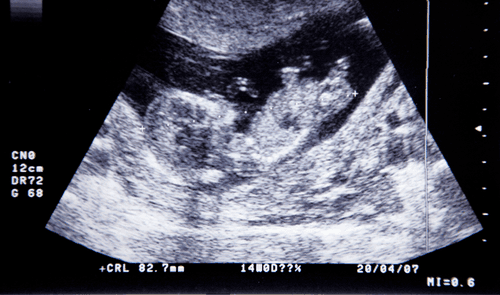

- Det er også muligt at hjælpe befrugtningen på vej ved hjælp af den såkaldte IVF-metode (In Vitro Fertilisation). Her starter man med at stimulere kvindens produktion af æg ved hjælp af hormoner. Lige før kvindens ægløsning, udtages de modne æg fra kvinden, hvorefter de befrugtes i en glasskål, ved at ægget tilføres 50.000-100.000 sædceller. To til fire døgn senere indføres et til to befrugtede æg i kvindens livmoder.